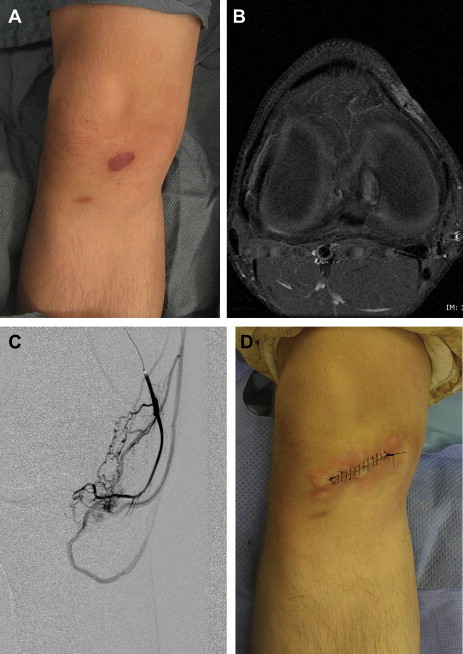

Because the AVM is not removed, almost all lesions eventually will expand after treatment; most older studies suggest that multiple embolizations do not lower the rate of recurrence, although newer embolic agents may offer more lasting results. Stage I AVM has a lower recurrence rate than higher-staged lesions. Most recurrences occur within the first year after embolization and 98% reexpand within 5 years; although this may reflect results obtained with older embolic agents. Patients who have not exhibited enlargement 5 years following embolization are more likely to have long-term control. Despite the high likelihood of reexpansion, embolization can effectively palliate an AVM by reducing its size, slowing expansion, and alleviating pain and bleeding ( Fig. 1 ). The aim of preoperative embolization is to reduce blood loss during extirpation.

Resection of AVM has a lower recurrence rate than embolization and is considered for well-localized lesions ( Fig. 2 ) or to correct focal deformities (ie, bleeding or ulcerated areas, labial hypertrophy) ( Figs. 3 and 4 ). Wide extirpation and reconstruction of a large, diffuse AVM should be exercised with caution because (1) cure is rare and the recurrence rate is high; (2) the resulting deformity is often worse than the appearance of the malformation; and (3) resection is associated with significant blood loss, iatrogenic injury, and morbidity.